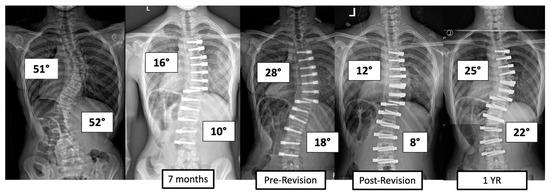

There were four major complications (10.8%), including one readmission and three patients who required re-operation. Patient 1 underwent re-operation due to radiculopathy caused by a screw tip impinging on a nerve root in a lumbar foramen requiring screw revision and replacement of the tether. At 3 years post operation, they have a broken tether at one level, but no further revision is needed. Patient 2 had progression of a previously uninstrumented thoracic minor curve which progressed following lumbar tether breakage. This was revised with fusion of the previously untreated thoracic curvature and the addition of a second row of screws and second tether for the thoracolumbar construct (Figure 3). Patient 3 had overcorrection of the thoracolumbar curvature and adding on of the thoracic. As a result, the tether was released in the thoracic region and the thoracolumbar tether was revised (Figure 4). One patient (3%) required readmission due to an inability to tolerate post-operative pain medication. During admission, pain was controlled, and they were discharged without sequela.

Figure 4.

This is an 11-year-old female who experienced overcorrection of the thoracolumbar curvature and adding on of the thoracic. A revision operation was performed to release the tether in the thoracic region and revise the thoracolumbar tether.